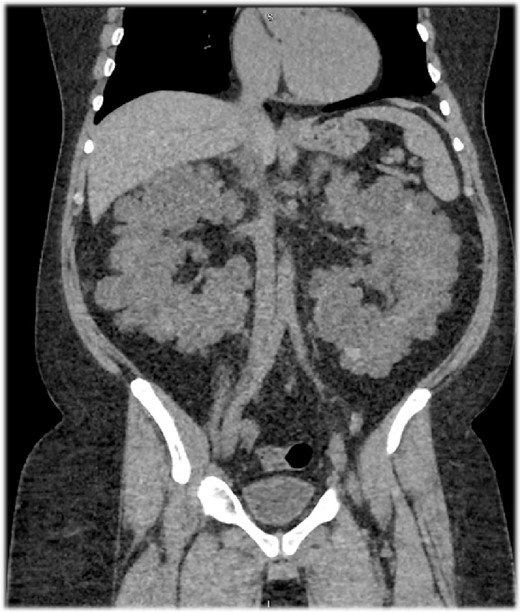

A 46-year-old Saudi male with a history of ADPKD and ESRD was assessed for a living-related kidney transplant due to his significantly enlarged kidneys, causing discomfort and limited space to implant a new kidney (Fig. 1). He weighed 111.1 kg—reflecting a BMI of 38 kg/m2—with a serum creatinine of 783 μmol/L and an eGFR of 7 ml/min/1.73 m2.

A sagittal section of a non-contrast computed tomography (CT) scan showing enlarged polycystic kidneys with the left and right kidneys measuring 16.5 × 10.1 × 11.3 cm3 with an estimated volume of 1.35 L and 16 × 9.4 × 13 cm3 with an estimated volume of 1.22 L, respectively. Both kidneys were filled with numerous cysts, replacing the normal renal parenchyma.